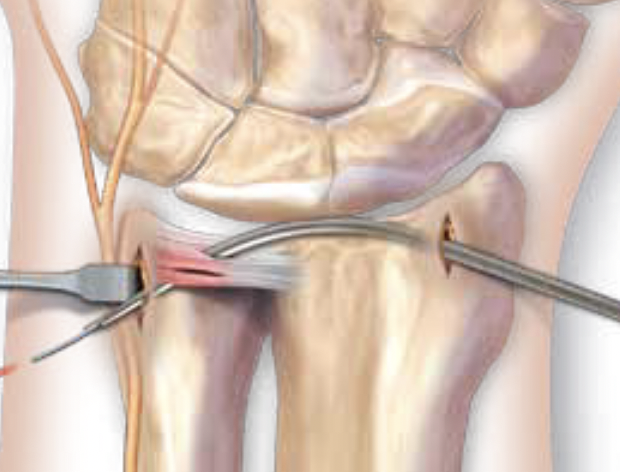

Radial sided TFCC tears

Radial sided repair

- more difficult

- drill holes through dorsal radius into ulna fossa

- use suture retriever